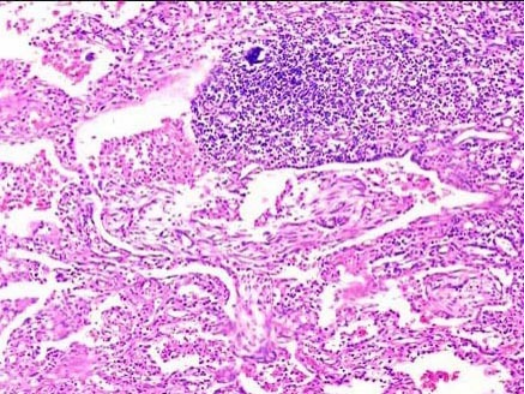

患者,1个月前因高热,咳铁锈色痰伴呼吸困难入院。经治疗临床症状消失,但肺下叶实变灶不消失,手术切除,镜检如图所示,正确的诊断是( )

C.肺肉质变

正确答案C